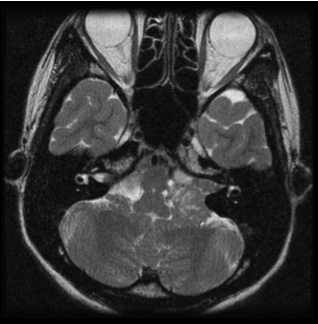

図1は若い男性で大きめの腫瘍であったため手術にて摘出しました。術前聴力は良好で、術後もほぼ聴力は変化なく、また顔面神経麻痺も出現していません。

図1:20代男性 聴神経腫瘍

(左図)術前MRI:術前聴力は10dB

(右図)術後MRI:内耳道に筋肉片がおかれている術後聴力は温存16dB 顔面麻痺はなし